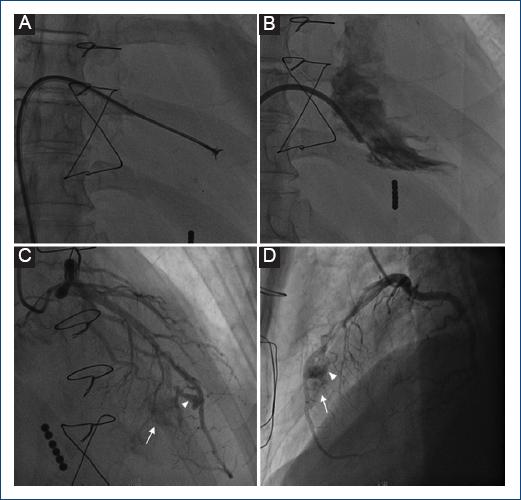

Tres semanas posteriores a la cirugía se realizó biopsia endomiocárdica (BEM) (Fig. 1A), por abordaje femoral, con obtención de seis muestras del septum interventricular (medial y apical) de ventrículo derecho, cuyo resultado arrojó rechazo leve tipo 1 Quality 2, realizándose seguimiento clínico estrecho. La ventriculografía posbiopsia descartó complicaciones inmediatas (Fig. 1B). Tres semanas después de la primera BEM se realizó angiografía coronaria invasiva (ACI) (Fig. 1 C D) con hallazgo de dos pequeños aneurismas sobre arteria descendente anterior y fístula coronaria que comunicó arteria descendente anterior con el ventrículo derecho; descartándose estenosis coronaria significativa. El paciente no presentó síntomas asociados, por lo cual se decidió seguimiento clínico.

Figura 1 A: toma de biopsia endomiocárdica (BEM) en septum de ventrículo derecho (apical y medio). B: ventriculografía posbiopsia. C y D: angiografía coronaria invasiva (ACI) en el año 2013. Dos pequeños aneurismas (puntas de flecha) de dimensiones 5.9 x 2.8 y 3.1 x 1.5 mm sobre arteria descendente anterior y fístula coronaria (flecha) que comunica sus ramos septales con el ventrículo derecho.